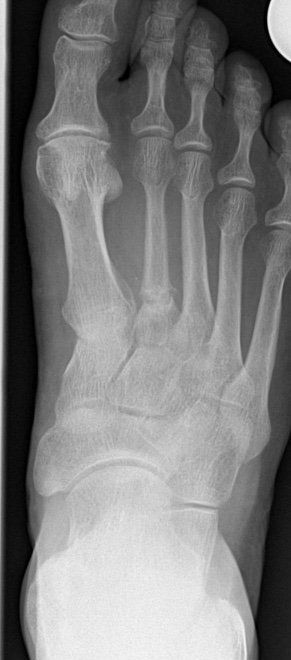

Röntgen

- Bildgebende Unter-suchungsverfahren ersetzen nicht die klinische Diagnostik sondern ergänzen sie.

- In der Praxis werden die Röntgenaufnahmen auf digitalem Weg erstellt.

- Das Verfahren bietet neben der geringeren Strahlen-belastung als im früher üblichen Film/Folien-verfahren auch die Möglichkeit dem Patienten jederzeit eine CD mit seinen Röntgenbildern erstellen zu können um so Doppel-untersuchungen zu ver-meiden.

- Natürlich werden auch bereits vorhandene Röntgenbilder zur Untersuchung mit herangezogen.